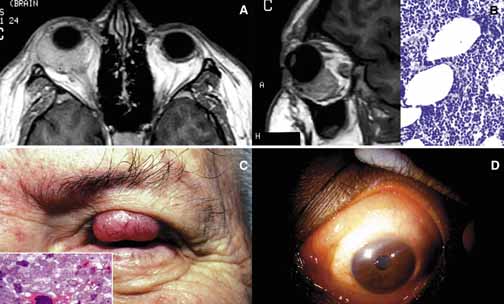

Sjögren syndrome (SS) consists of a triad of symptoms including dry eyes (keratoconjunctivitis sicca), dry mouth (xerostomia), and “dry joints” (arthritis).120 Primary SS is not associated with other connective tissue diseases; however, secondary SS symptoms overlap with the manifestations of systemic lupus erythematosis, polymyositis, polyarteritis nodosa, scleroderma, and rheumatoid arthritis.121 Like many other autoimmune diseases, SS does not have a clear cut etiology, however, primary SS is considered a mononuclear inflammatory vasculopathy closely linked to HLA-DR3 and HLA-DRw52; secondary SS associated with rheumatoid arthritis is linked to HLA-DR4.122 Many viruses, including Epstein-Barr, CMV, HIV, and hepatitis-C, have been reported to have an etiologic role in SS. Immune complex formation and deposition are considered to be the physiopathology of cutaneous and ocular vasculitis.123

Histopathology of the conjunctiva as well as the lacrimal gland is nonspecific consisting of lymphocytic and plasma cell infiltrates surrounded by eosinophilic basement membrane like material (Table 2). These units are called epimyoepithelial islands and are considered to be diagnostic of SS.124 Lacrimal gland also reveals acinar atrophy and increased fibrosis surrounding the ductules125 (Fig. 12). Diagnosis of SS is based on minor salivary gland biopsy rather than the biopsy of the lacrimal gland, because the latter procedure is more invasive and carries a higher morbidity.126

Fig. 12 Sjögren disease. A pateint with bilateral enlargement of lacrimal glands that was involving the left side more than the right (A,B). Minor salivary gland biopsy from the lower lip revealed infiltration of eosynophils, lymphocytes and plasma cells. The biopsy was sufficient to make the diagnosis combined with the clinical picture. The same patient developed orbital lymphoma, which is depicted in frame B, 3 years after the diagnosis of Sjögren disease.

Keratoconjunctivitis sicca is the most common presentation of SS in the eye occurring in approximately 90% of patients. Diminished tear meniscus and decreased tear break up time (BUT) with diminished tear production documented with Schirmer strips are common findings. Less commonly, patients develop episcleritis/scleritis in primary type of SS.127 Because of peripheral and central nervous system involvement, optic neuritis and internuclear ophthalmoplegia may be seen in these patients. From the orbital standpoint, the asymmetrical presentation of the disease may be confused with an orbital lymphoma or sarcoidosis. In most cases, however, the disease presents with bilateral enlargement of the lacrimal glands and with the presence of other symptomatology SS is easy to diagnose (Fig. 12). It should be kept in mind, however, that SS patients have an increased risk of developing B-cell lymphomas in the salivary glands and cervical lymph nodes. This association was not found to be true for the lacrimal gland. However, orbital lymphoma that may mimic the presentation of SS should always be considered in the differential diagnosis.